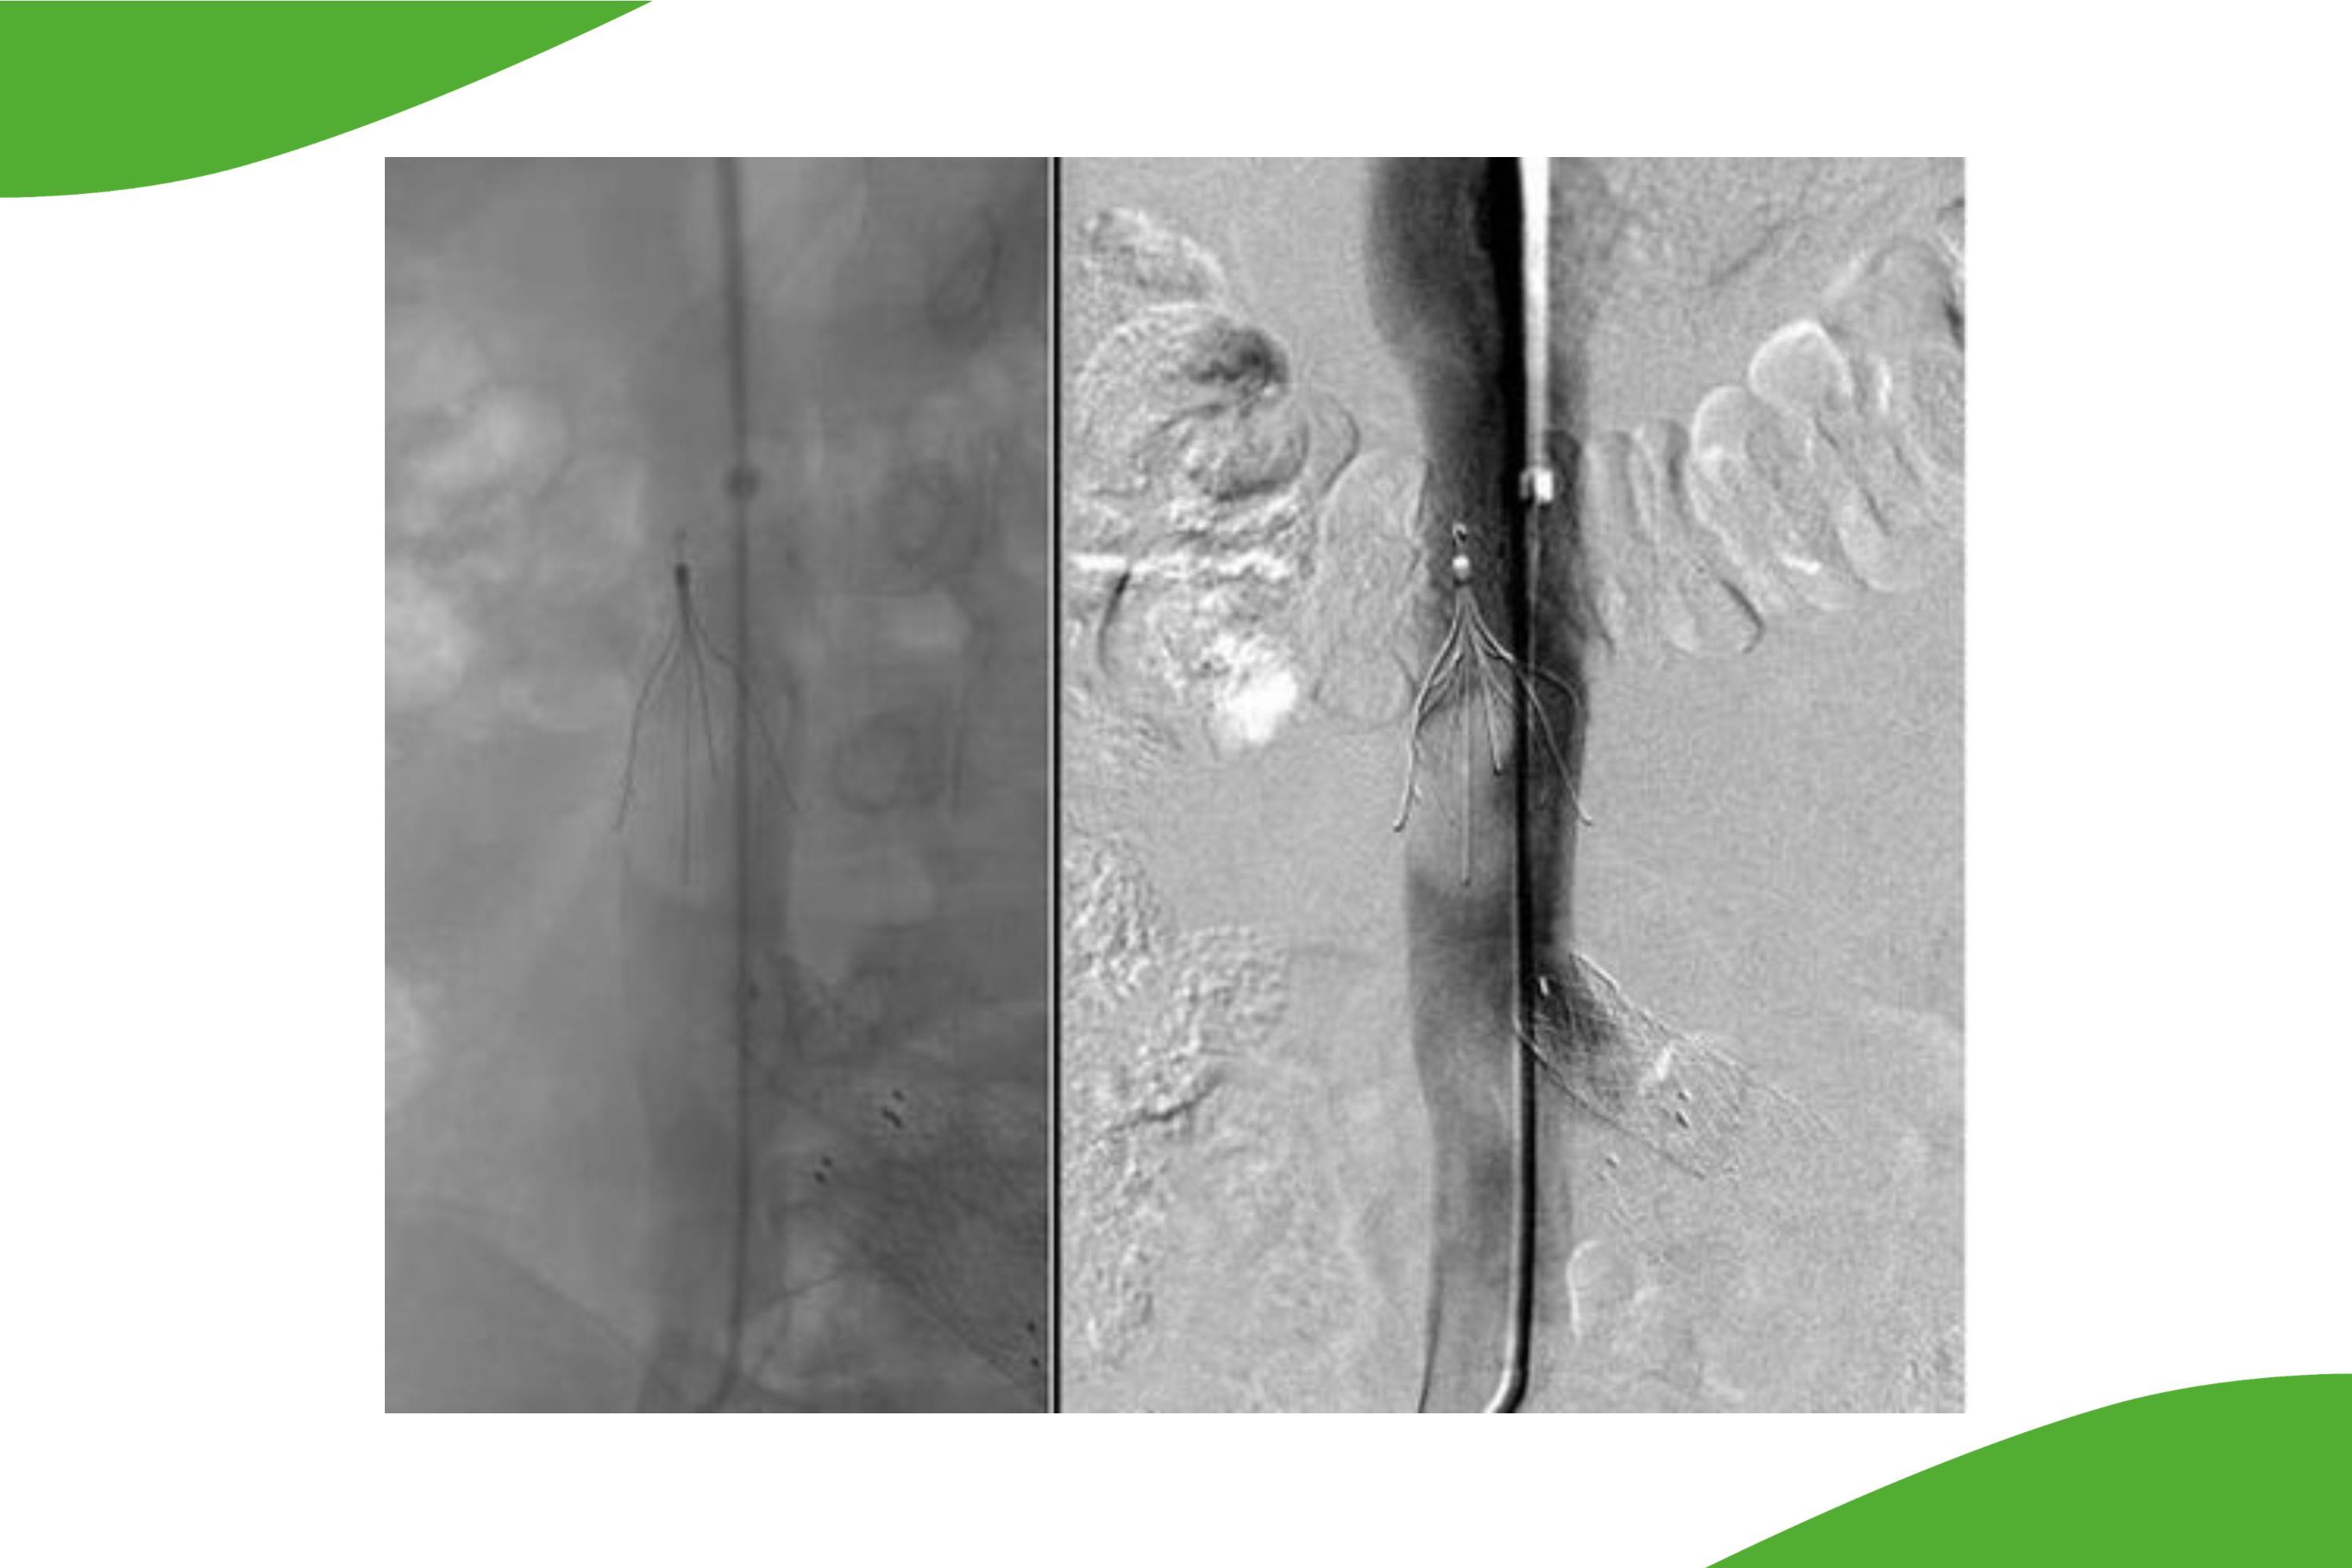

Grafische Dartstellung: Distaler Verschluss der Oberschenkelarterie bis ins Bewegungssegment reichend (weiße Pfeile). Nach der durchgeführten Artherektomie und der anschließenden Behandlung mit einem medikamentenbeschichteten Ballon zur perkutanen transluminalen Angioplastie ist die Durchblutung wiederhergestellt.

Grafische Dartstellung einer Artherektomie, der Eingriff wird im Text beschrieben.

Grafische Darstellung eines Verschlusses der Kniegelenksarterie (Pfeile). Erst in den Spätaufnahmen füllten sich die Unterschenkelgefässe. Klinisch lag eine kritische Durchblutungsstörung vor. Geeignetes körpereigenes Ersatzmaterial (Venen) für einen Bypass lag nicht vor, ferner reduzierte OP-Fähigkeit. Rechts: Stent-PTA mit gewebtem Stent. Die alleinige Dilatation hatte keine ausreichennde Aufweitung ergeben. Nach Implantation eines gewebten Stentes sehr gute Gefässrekonstruktion. Die Beschwerden waren rasch rückläufig.